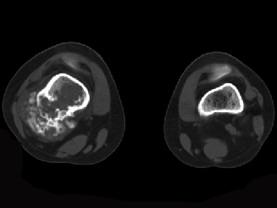

男,34岁,大腿下段疼痛2年,可摸到肿块,请结合所提供图像,选择最佳选项 ( )A、纤维肉瘤B、巨细胞瘤C、软骨肉瘤D、软骨瘤...

问题 男,34岁,大腿下段疼痛2年,可摸到肿块,请结合所提供图像,选择最佳选项 ( )

选项 A、纤维肉瘤 B、巨细胞瘤 C、软骨肉瘤 D、软骨瘤 E、骨肉瘤

答案 C